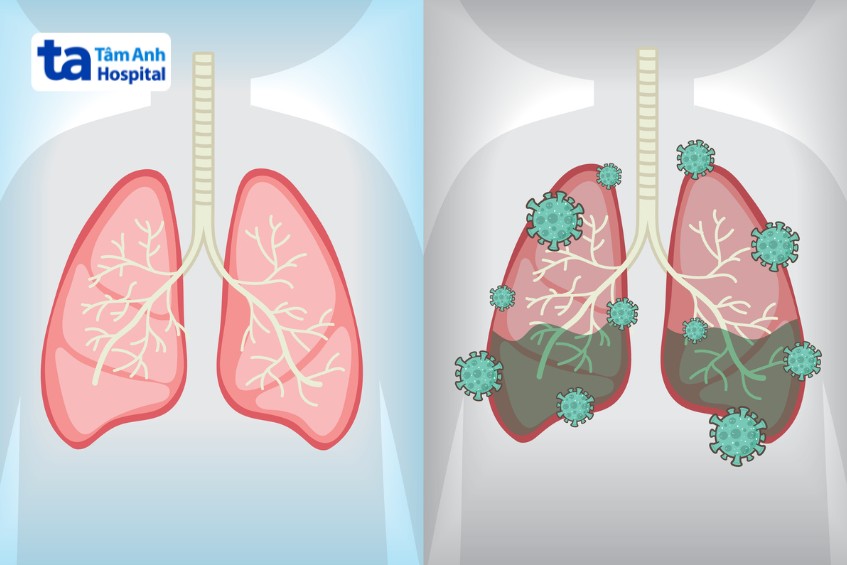

Viêm phổi ở trẻ sơ sinh là tình trạng cấu trúc phổi (như nhu mô, mô kẽ, mạch máu hoặc màng phổi,…) bị tổn thương do sự tấn công của các tác nhân lây nhiễm. Bệnh có thể khởi phát sớm ngay sau sinh hoặc muộn hơn, với nhiều mức độ nặng nhẹ tùy từng trường hợp. Vậy trẻ sơ sinh bị viêm phổi có nguy hiểm không? Bệnh gây ảnh hưởng như thế nào đến sức khỏe của trẻ?

Viêm phổi ở trẻ sơ sinh, đặc biệt là viêm phổi do vi khuẩn có thể gây biến chứng tràn dịch màng phổi ở trẻ. Biến chứng này xảy ra khi trẻ không đáp ứng hoàn toàn với các phương pháp điều trị thông thường. Vi khuẩn lan ra màng phổi, tích tụ và gây nhiễm trùng, tạo thành ổ mủ, khiến trẻ khó hô hấp, nguy hiểm tính mạng. (5)